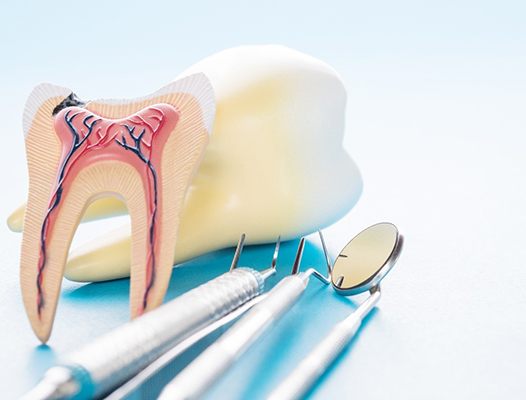

What is a Root Canal?

A root canal, also known as endodontic treatment, is designed to remove infection from deep inside a tooth. Once this step is completed, the tooth is sealed and prepared for a porcelain crown that will protect the remaining tooth structure.

To understand how a tooth can become infected in the first place, we first need to examine the structure of a tooth. Each tooth consists of three layers. The outermost layer is called enamel. This extremely hard surface gives your smile an attractive sheen.

Below the enamel is dentin, a somewhat softer and slightly porous material. At the center of each tooth is the pulp chamber. Here, blood, lymph and nerve tissue transport nutrients to the tooth and remove waste through root canals that connect to your bloodstream.

Normally, the chamber and canals are protected by the enamel and dentin. However, if you have a large cavity, a crack or a loose filling, then bacteria can migrate to the interior. When this happens, infection can begin.